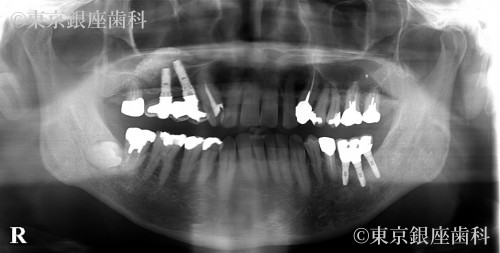

右上4番の動揺があり予知性が低いため同意を得て抜歯。サイナスリフトを併用した2本のインプラント埋入で右上456番の3本の補綴を行う事とした。